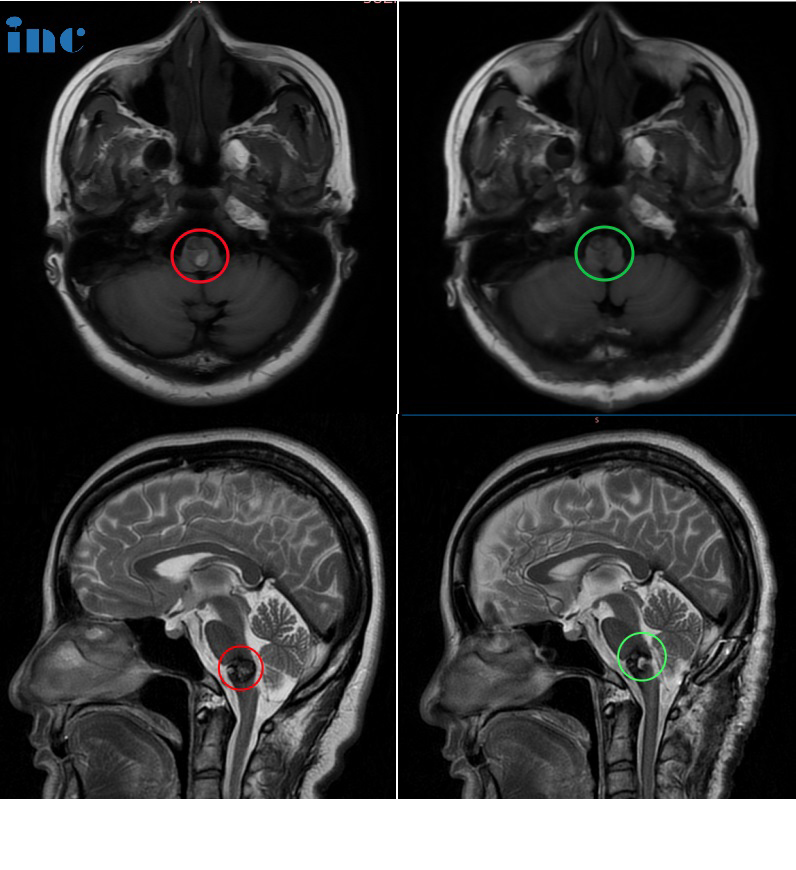

50岁女性-延髓海绵状血管瘤

28岁女性-脑干延髓海绵状血管瘤

19岁男孩-延髓海绵状血管瘤

32岁男性-延髓海绵状血管瘤

30岁女性-延髓-颈髓海绵状血管瘤